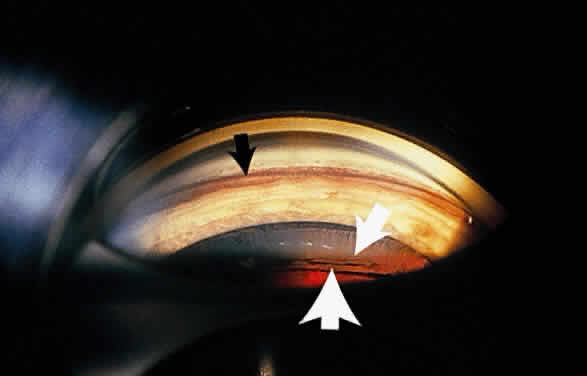

Some patients with XFS exhibit phacodonesis and subluxation of the lens, apparently resulting from degenerative changes in the zonular fibers.45–47 (Fig. 3) Spontaneous dislocation of the lens into the vitreous has been reported.48 In 1970, Bartholomew described 22 spontaneously displaced lenses in 19 patients with the disorder.45 Sixteen of the lenses were subluxated inferiorly. In these eyes, he visualized superior zonular fibers that were coated with exfoliative material and further noted that the zonular breaks generally were present at the ciliary body attachments and not at the lens, leading him to hypothesize that the main degenerative process occurred at the insertion of the zonular fibers to the basement membrane of the ciliary body epithelium. By electron microscopic examination, Schlötzer-Schrehardt and Naumann noted disruption of zonular fiber structure at the ciliary body insertion sites in eyes with XFS but also observed abnormalities at the attachments to the anterior lens capsule.46

Exfoliative material also may be seen on the ciliary processes and zonules (Fig. 8). Using a modified method of gonioscopy known as cycloscopy, Mizuno and Muroi documented exfoliative material on the zonules and ciliary processes in all 31 eyes with clinical evidence of exfoliation.12 They further note that in patients with clinically unilateral exfoliation, more than half (17 of 31) of the fellow eyes demonstrated exfoliative material on the ciliary processes and zonules, thus establishing subclinical evidence of exfoliation in clinically “uninvolved” eyes.